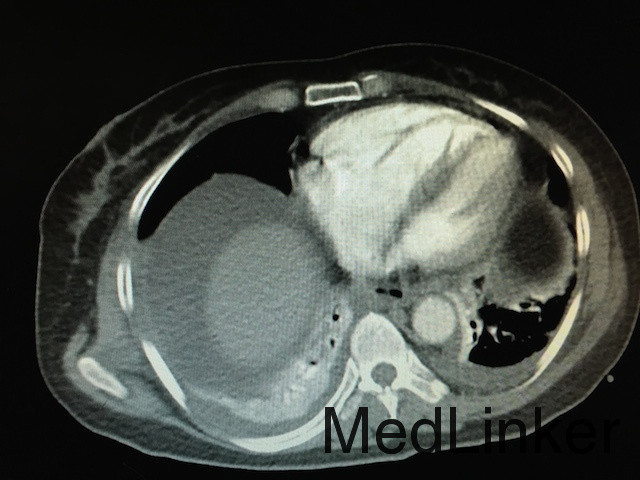

随访:患者病情稳定后行胸部CTA如下图:双肺动脉分支栓塞,双肺片状影,双肺下叶局部膨胀不全,双侧胸腔积液。转至ICU后,患者生命体征稳定,暂不考虑行溶栓治疗,予以低分子肝素继续抗凝治疗,复查ECG后示:Q波深度较浅减低,T波恢复正常,抗凝有效。 讨论:患者为PCNL术后,由于手术时间长,且术中由于行结石位,下肢长时间受压,加上患者年龄大,很容易形成深静脉血栓,患者下地导致血栓脱落,阻塞肺部血管,造成肺动脉栓塞。